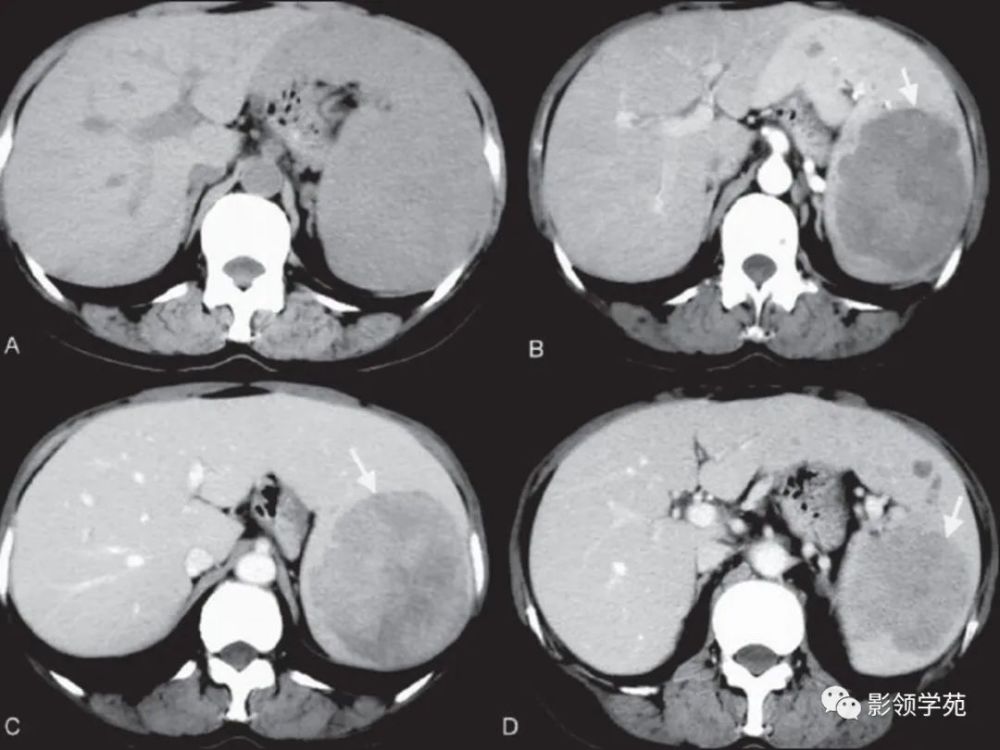

副脾CT

副脾CT,副脾CT

副脾ct图片